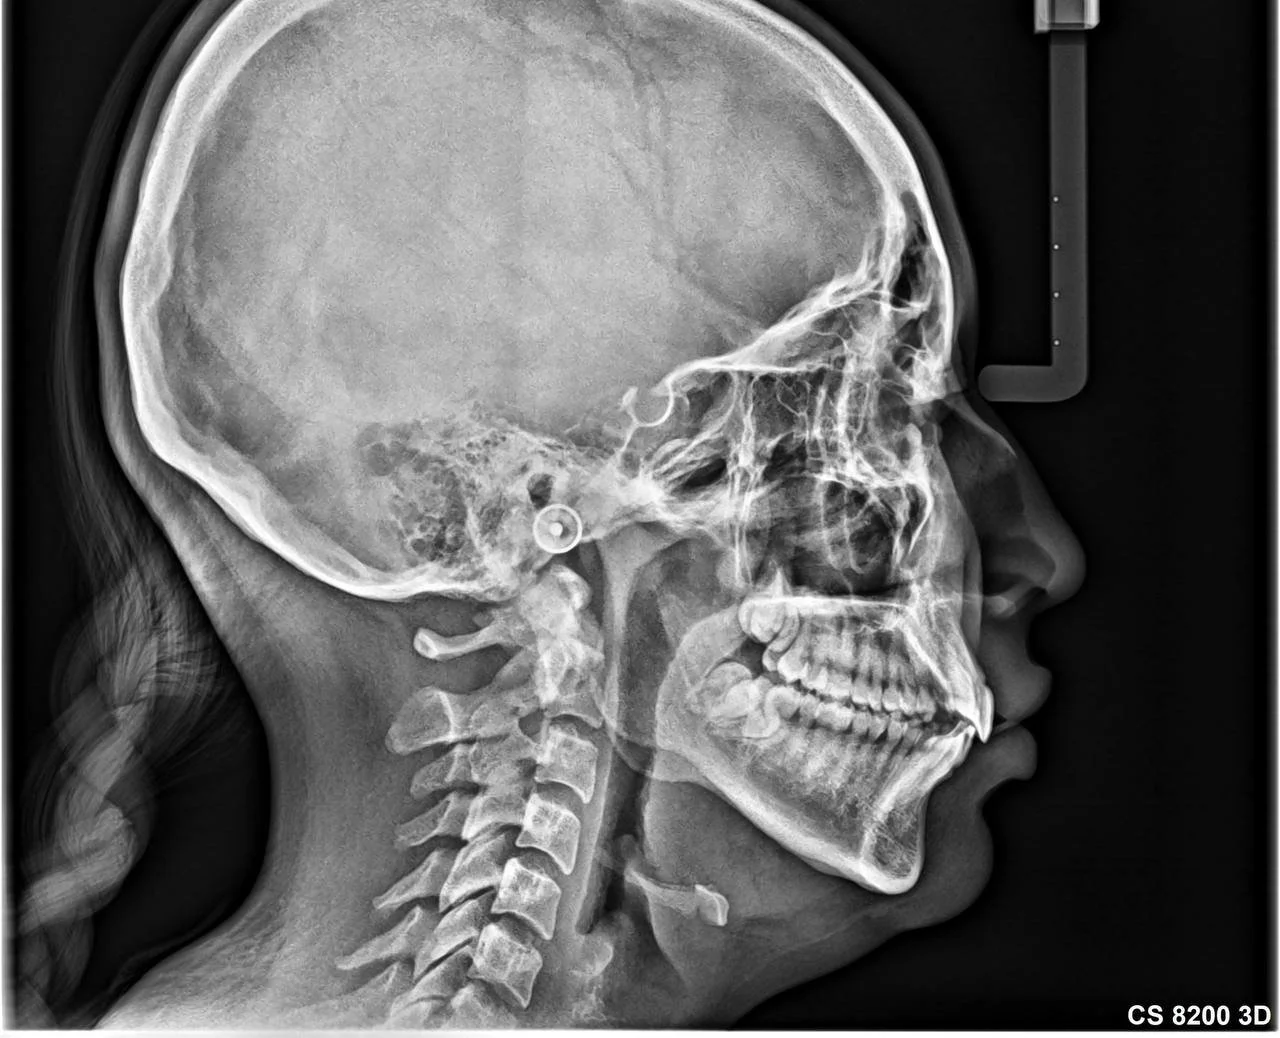

Lateral de Cráneo

La radiografía lateral de cráneo 2D es un estudio fundamental en ortodoncia y diagnóstico dentofacial, ya que permite evaluar las relaciones óseas, dentales y el crecimiento facial de forma precisa.

Gracias a nuestra tecnología digital de alto nivel, obtenemos imágenes nítidas y confiables, con una baja dosis de radiación para el paciente.